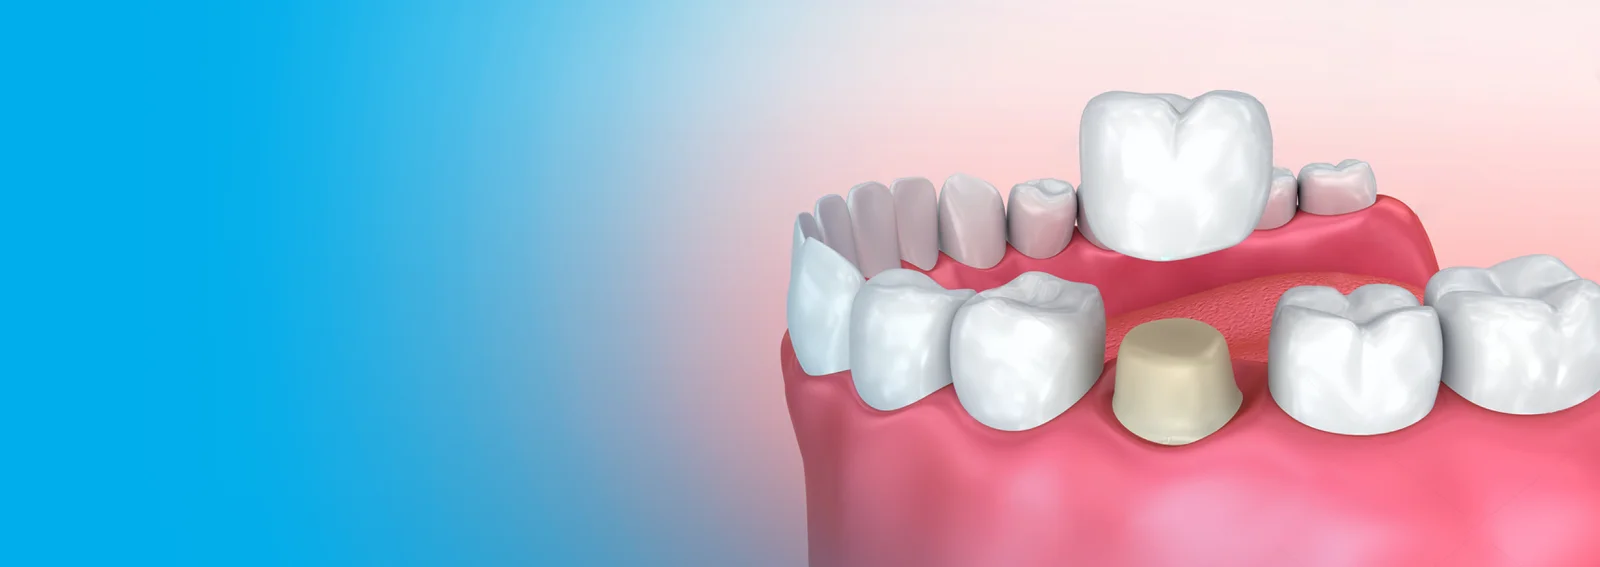

Crowns:

Dental crowns are tooth-shaped caps that are placed over a damaged or decayed tooth. They are used to restore the tooth's shape, size, strength, and appearance. Crowns can be made from various materials, including porcelain, ceramic, metal, or a combination of these materials. The choice of material depends on factors such as the location of the tooth, the extent of damage, and aesthetic considerations.